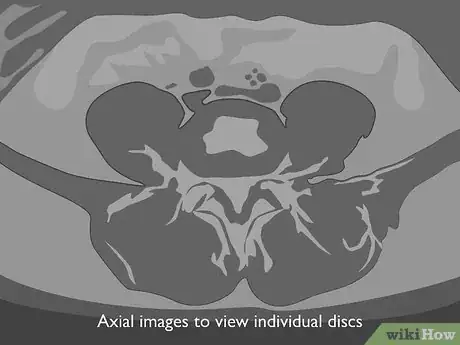

4Look at axial images to view individual discs. If one or more of your discs show an abnormality, you may have axial images that show that disc in greater detail. With an axial image, you're looking at the top of the disc as seen from above.[5]

- You can tell more about the size of the nerve canals by looking at an axial image. Your doctor may use an axial image to get a clearer picture of a herniated disc.